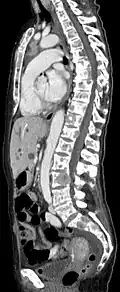

- Vergleich CT / MRT bei osteolytischen Metastasen eines Mammakarzinoms in der Wirbelsäule

Sagittal rekonstruierte CT, Darstellung im Knochenfenster. Da die Patientin multiple Metastasen in allen Körperregionen hatte, konnte sie die Arme nicht für die Untersuchung nach oben nehmen, weshalb die Hände mit abgebildet sind. -

Sagittal rekonstruierte CT, Weichteilfenster. Neben den Metastasen in der Wirbelsäule, die teilweise nach hinten in den Spinalkanal einwachsen, auch Metastasen im Brustbein. Zusätzlich Lebermetastasen. -